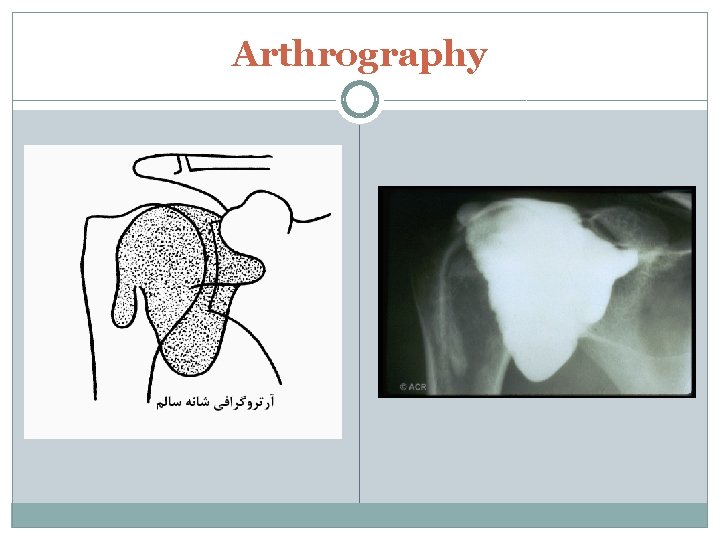

Arthrography

Arthrography